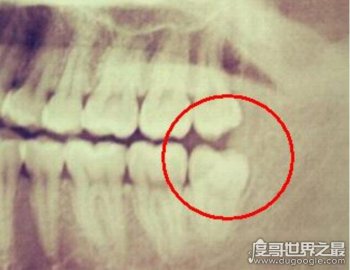

不需要拔的智齒圖片

看見這幅圖了嗎? 如圖所示,這種智齒完全不用拔掉,因?yàn)樗鼈円呀?jīng)非常對(duì)稱地長(zhǎng)了,并且生長(zhǎng)得很好,不會(huì)影響到你的口腔,也不會(huì)產(chǎn)生不良反應(yīng),所以像這種長(zhǎng)得比較整齊的智齒完全不用拔掉,拔掉只會(huì)讓你后悔!